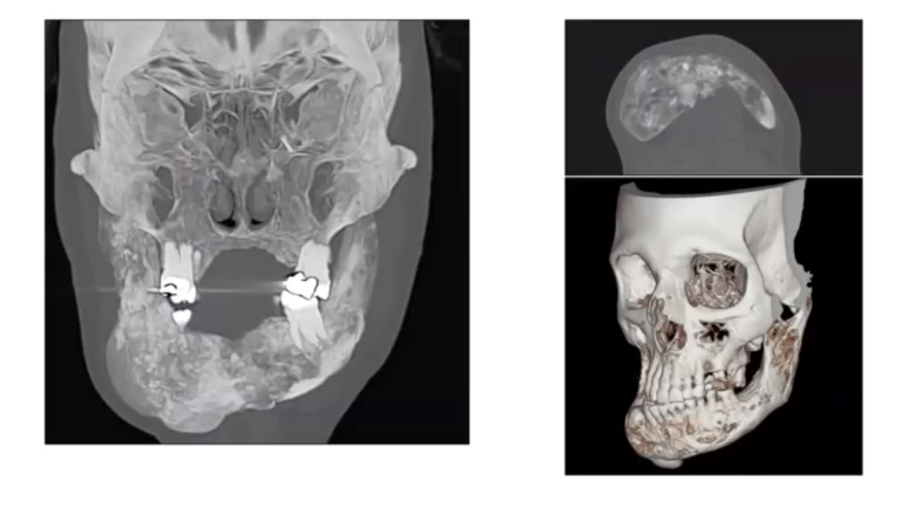

For example, free flaps are normally indicated for circumferential pharyngoesophageal reconstruction, class III or higher defects of the maxilla, and composite defects in mandibular reconstruction. When used for salvage total laryngectomy, they reduce the incidence of pharyngocutaneous fistulae.

Particularly where a flap is used to increase bulk, some degree of retraction normally occurs. This process can continue for a very long time. Therefore, in cases where a massive resection of the tongue and mandibulotomy have been necessary, a slightly-oversized ALT flap (with bone taken from the femur, if necessary ) will allow for shrinkage over a period of ten or more years.